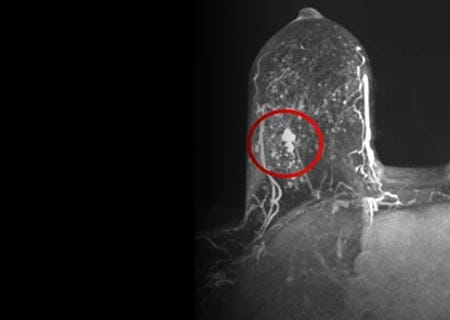

Contrast Enhanced Ultrasound Imaging Holds Promise for Prostate Cancer Detection Treatment